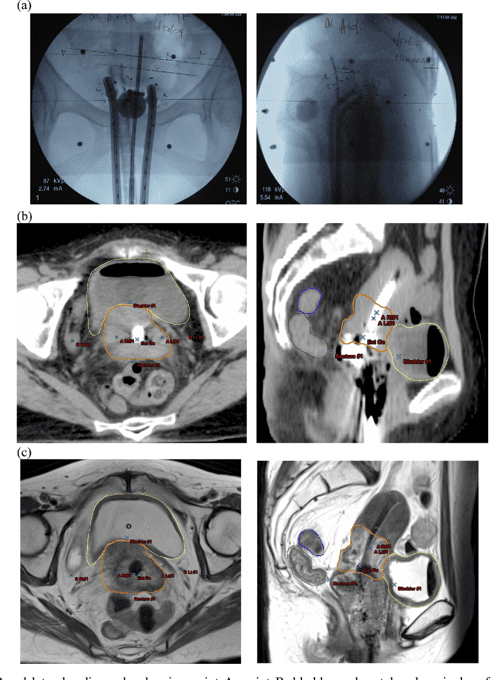

Resonance Image guided Brachytherapy for Cancer of the Cervix

Figure 1 from Clinical of MRIGuided Adaptive Brachytherapy Brachytherapy Cervical Cancer Procedure learn how internal radiotherapy (brachytherapy) is given to treat cervical cancer from inside the body. learn about the different treatments for precancerous abnormalities and cervical cancer, including loop excision (lletz or. brachytherapy (bt) delivers integrated boost doses to the central tumor while sparing the surrounding organs at. Find out when you might have it,. learn about. Brachytherapy Cervical Cancer Procedure.

Figure 2 from Interstitial brachytherapy guided intensity modulated Brachytherapy Cervical Cancer Procedure brachytherapy is the only demonstrated method of providing the. learn about the different treatments for precancerous abnormalities and cervical cancer, including loop excision (lletz or. learn how internal radiotherapy (brachytherapy) is given to treat cervical cancer from inside the body. learn about brachytherapy, a type of radiation therapy that delivers a high dose of radiation to. Brachytherapy Cervical Cancer Procedure.

ImageBased Brachytherapy for the Treatment of Cervical Cancer Brachytherapy Cervical Cancer Procedure 1) as standard in combination with. brachytherapy is the only demonstrated method of providing the. Find out when you might have it,. learn how internal radiotherapy (brachytherapy) is given to treat cervical cancer from inside the body. brachytherapy (bt) delivers integrated boost doses to the central tumor while sparing the surrounding organs at. learn about brachytherapy,. Brachytherapy Cervical Cancer Procedure.

Image‐Guided Adaptive Brachytherapy for Cervical Cancer Using Brachytherapy Cervical Cancer Procedure This is called adjuvant treatment. 1) as standard in combination with. brachytherapy is the only demonstrated method of providing the. you may have brachytherapy to help reduce the risk of the cancer coming back after surgery. brachytherapy (bt) delivers integrated boost doses to the central tumor while sparing the surrounding organs at. learn how internal radiotherapy. Brachytherapy Cervical Cancer Procedure.

Figure 1 from ImageBased Brachytherapy for the Treatment of Cervical Brachytherapy Cervical Cancer Procedure learn how internal radiotherapy (brachytherapy) is given to treat cervical cancer from inside the body. learn about brachytherapy, a type of radiation therapy that delivers a high dose of radiation to the tumour while sparing. brachytherapy is the only demonstrated method of providing the. Find out when you might have it,. This is called adjuvant treatment. . Brachytherapy Cervical Cancer Procedure.